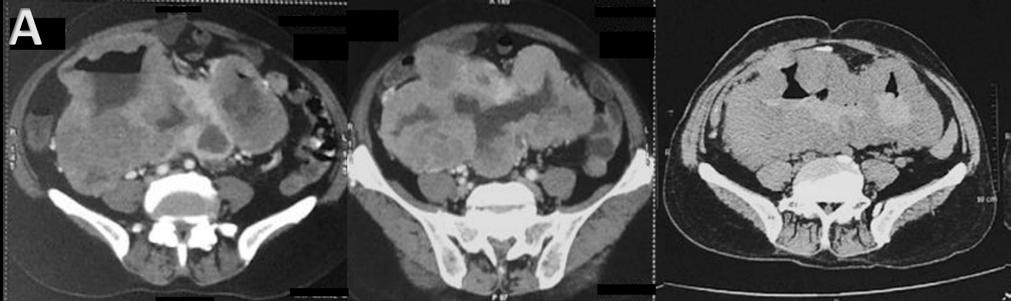

Therefore, having preoperative knowledge of the likelihood of recurrence would assist in selecting the most suitable liver transplant recipients, potentially avoiding unnecessary surgeries, and improving patient prognosis and organ allocation. In this context, radiomics, which involves high-throughput data extraction from medical images, holds great promise.3 However, there is ongoing debate regarding the optimal data selection strategy, as factors such as the choice of contrast phase and volume of interest (VOI) can significantly impact radiomic analysis results.4-6 Therefore, the authors’ study aimed to investigate how these factors influence radiomic features (RF), to identify the optimal combination for predicting HCC recurrence in liver transplant candidates.

Liver transplant candidates from 2010–2019, with waitlist placement CT scans showing nodules suspicious for HCC, according to the Liver Reporting and Data System (LI-RADS) criteria7 (LR-4/-5), and histologically confirmed after the transplant, were retrospectively included. Patients who had previously undergone locoregional procedures, exhibited tumour in vein, or had poor image quality were excluded from the analysis. HCC nodules were contoured

across arterial, venous, and delayed phases, with or without peritumoral region of 5, 10, and 15 mm. An area of ‘background’ liver parenchyma, distant from the lesions, was also segmented in each phase.

A total of 107 RFs, both directly extracted from segmentations, and normalised for the ‘background’ parenchyma, were obtained using PyRadiomics (Python Software Foundation, Beaverton, Oregon, USA). The normalisation was conducted by calculating the ratio between the RFs extracted from the VOI, and those extracted from the background segmentation. These features were then compared with each other for inter-VOIs and inter-phase relative change, while autocorrelation was assessed using Spearman’s rank correlation coefficient. RFs with relative change <10% and rank correlation coefficient >0.90 were considered non-informative. Informative RFs with different distribution in patients with and without posttransplant recurrence were selected to build multiple logistic regression models. Prediction of post-transplant recurrence was assessed by comparing the areas under the curve from receiver operating characteristic analysis and goodness-of-fit, expressed as the value range of Tjur’s, McFadden’s, and Nagelkerke’s R2 .

RESULTS

The CT scans of 53 patients were selected, resulting in a total of 1,032 segmentations from 86 nodules, with eight (15%) recurrence cases. When varying VOIs and phases, the proportion of noninformative RFs, indicating insignificant differences between the VOI and liver background, were 14–26% and 16–34%, respectively, while 4% of RFs showed autocorrelation >0.90.

The selected informative RFs allowed the building of eight predictive models with adequate performance and goodness-of-fit,

each comprising 5–12 RFs, with an area under the curve of 0.77–0.90 (p<0.02) and pseudo-R2 values of 0.13–0.46. A predominance of models derived from the arterial phase was observed, utilising the nodule with or without a 5 mm peritumoral region as the VOI, followed by the venous phase, including a 10–15 mm margin after normalisation (Figure 1).

CONCLUSION

Selection of optimal VOI and contrast phase combination is critical to maximise post-liver transplant HCC recurrence prediction using quantitative CT imaging. Specifically, segmenting the nodule, eventually including a 5 mm peritumoral region, during the arterial phase, or the nodule with a 10-15 mm margin during the venous phase after normalisation against the liver background, appeared to be the most promising strategy.●